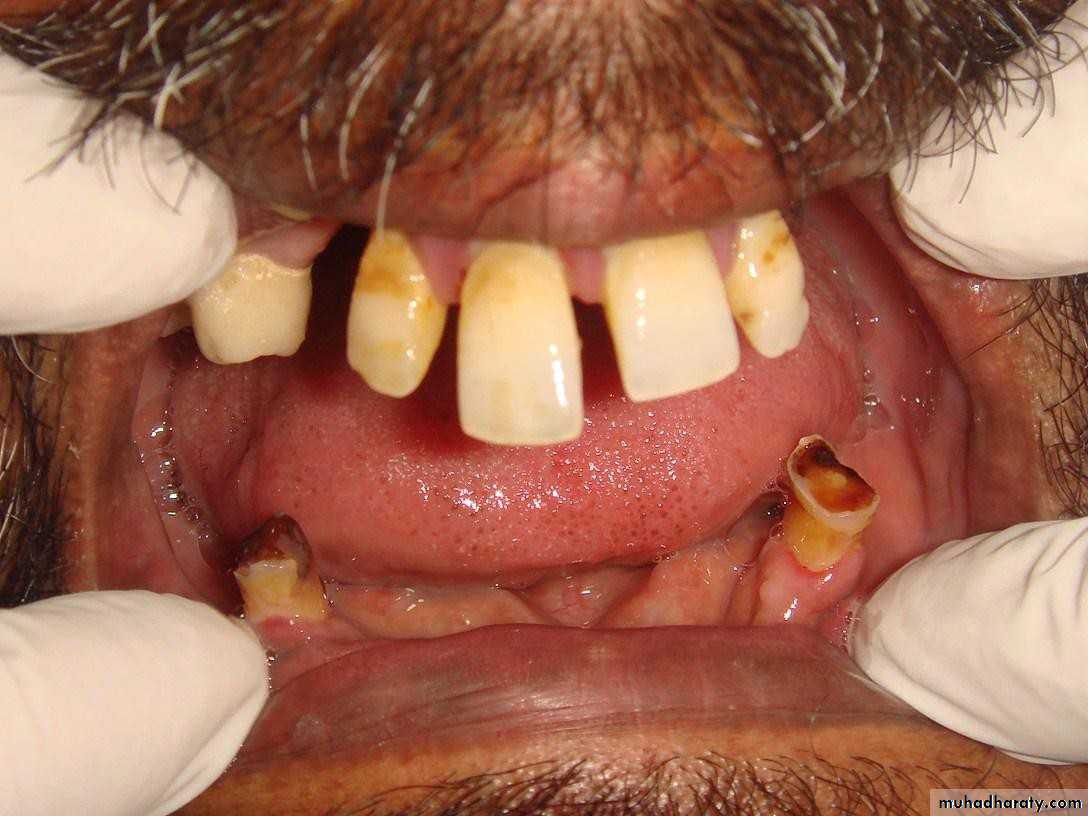

• 1) Few remaining teeth or teeth with an unfavourable distribution in the arch which precludes treatment with a removable P.D.

• 2) Severe loss of periodontal attachment in a patient who cannot afford a fixed partial denture

• 4) Significant tooth loss due to attrition.

• 5) Congenital absence of teeth i.e. Partial anodontia.